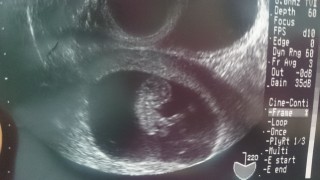

大きさ的に 週数変更で10週が9週に変更になりました。前回前々回と機械が違うようで 映りは少し見にくいかな。CRL2.04 、 2週間で倍になりました。 診察が押していた為、診察時間が短く残念だけど次回はもう少し見てたいなー